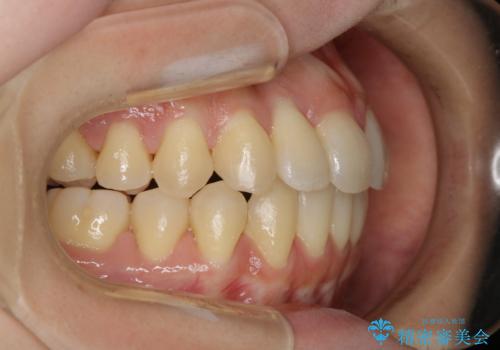

本来は外科ケース:インビザラインで前歯の重度がたつきとオープンバイトの改善

- 前歯のがたつきが気になるとご相談にいらした患者様です。矯正検査の結果、骨格的なズレが大きかったため当初の治療計画では外科矯正をご案内しました。ご本人が手術を望んでおらず、可能な限りの改善を目指すことを目標に治療を開始しました。

元々の骨格的なズレが大きかったため、当初は外科矯正をご提案していました。患者様の強いご希望により、非外科的な処置のみで可及的な改善を目指すことを目標に治療を行いました。以前よりもしっかり噛めるようになり、見た目も劇的に改善したことで大変ご満足いただけました。